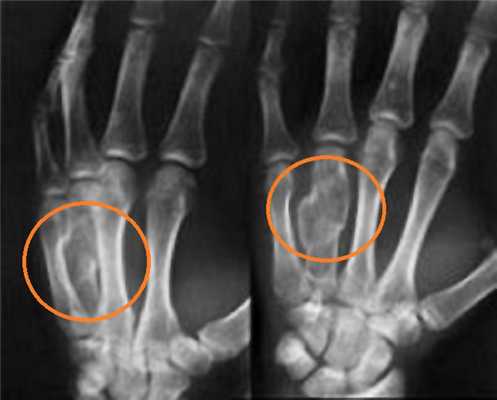

(Слева) На снимке определяется чрезмыщелковый перелом плечевой кости у женщины 63 лет после падения на выпрямленную руку. Линия перелома пересекает оба мыщелка, но не переходит на суставную поверхность. Имеется незначительное медиальное смещение дистального отломка, что является частой находкой при таких травмах.

(Справа) На фронтальной компьютерной томограмме с реформатированием без контрастирования у этой же пациентки подтверждается чрезмыщелковый ход перелома и отчетливо видно медиальное смещение дистального отломка. Кроме того, данные КТ подтверждают сохранность суставной поверхности плечевой кости.